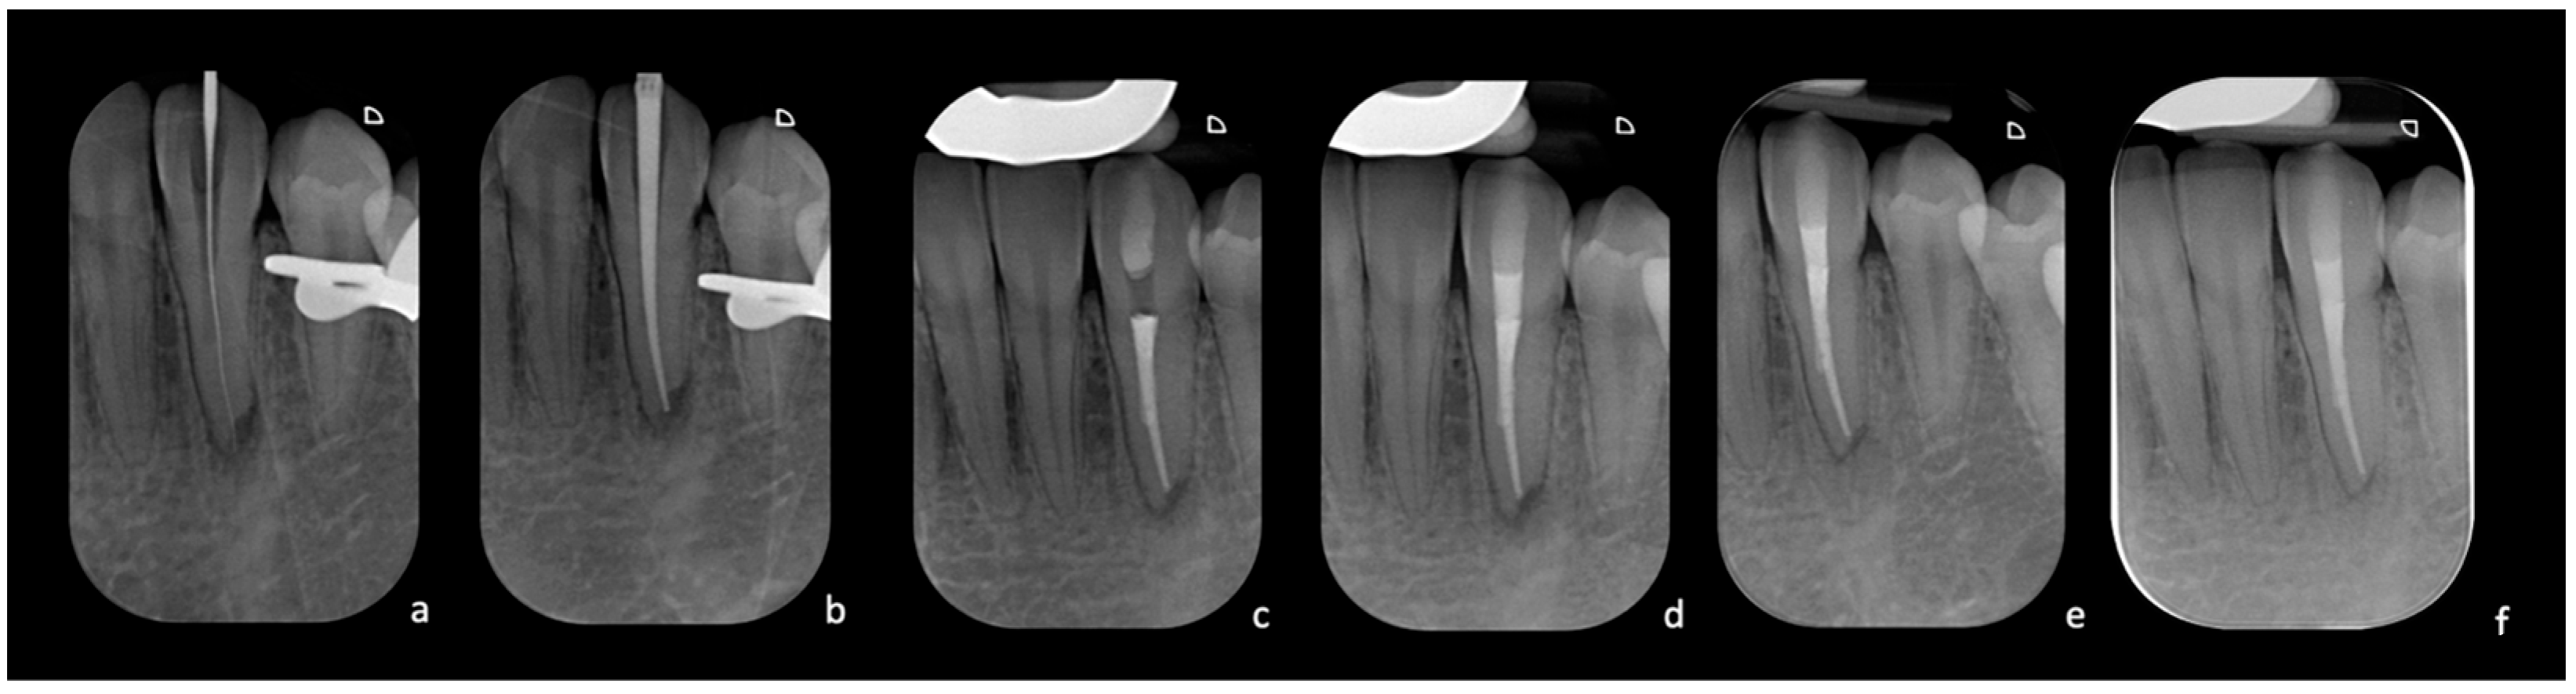

After local anesthesia (Articaine Septanest with adrenaline 1:200,000; Septodont, Saint-Maur-des-Fosses, France), the operating field was isolated with a rubber dam. The correct positioning and stability of the guide were preliminary checked, and the temporary filling material was removed. Once the template was positioned, a 0.8 mm drill (210L16 205 008 Komet Dental Gear Brassier GmbH & Co. KG, Lemgo, Germany) was mounted on the blue ring contra-angle and inserted through the guide cylinder. Once the planned target point was reached, the scouting phase was performed by a K-File #10 instrument (Dentsply Sirona Endodontics, Ballaigues, Switzerland) (Figure 3). The electronic working length was measured using the electronic apex locator (Ai-Pex, Gullin WoodPecker Medical Instrument Co., Ltd., Guilin, China), and a periapical X-ray was performed to confirm the working length. The canal was shaped with rotary Ni-TI files (EdgeEndo Platinum, EdgeEndo, Albuquerque, NM, USA), and the apex was finished with an F3 file (Protaper Ultimate, Dentsply Sirona, Charlotte, NC, USA). Detersion was performed by multiple rinses of 5% sodium hypochlorite (Niclor 5—Ogna, Muggio dental division, MB—Italy). To seal the shaped canal, the single-cone technique with hydraulic cement (Endosequence BC Sealer, Brasseler USA Savannah, GA, USA) was used; the cavity was then provisionally sealed with temporary cement. After four days, the patient did not show any sign of inflammation and symptoms, and restoration was then performed with adhesive (Optioned SoloTM Plus, Kerr Corporation, Orange, CA, USA) and a composite technique (Enamel plus, HFO Micerium, Rosbach, Germany). A final radiograph was performed at the end of the restorative procedures (Figure 4).

Figure 4. (a) Intra-operative X-ray of the K-file inserted at WL after locating the canal. (b) Intra-operative X-ray with the gutta-percha cone test. (c) Post-operative X-ray with completed root canal filling. (d) Radiograph taken after completing the coronal seal. (e) Radiographic control at three months with signs of improvement of the apical radiolucency. (f) Radiographic follow-up at two years with complete healing.